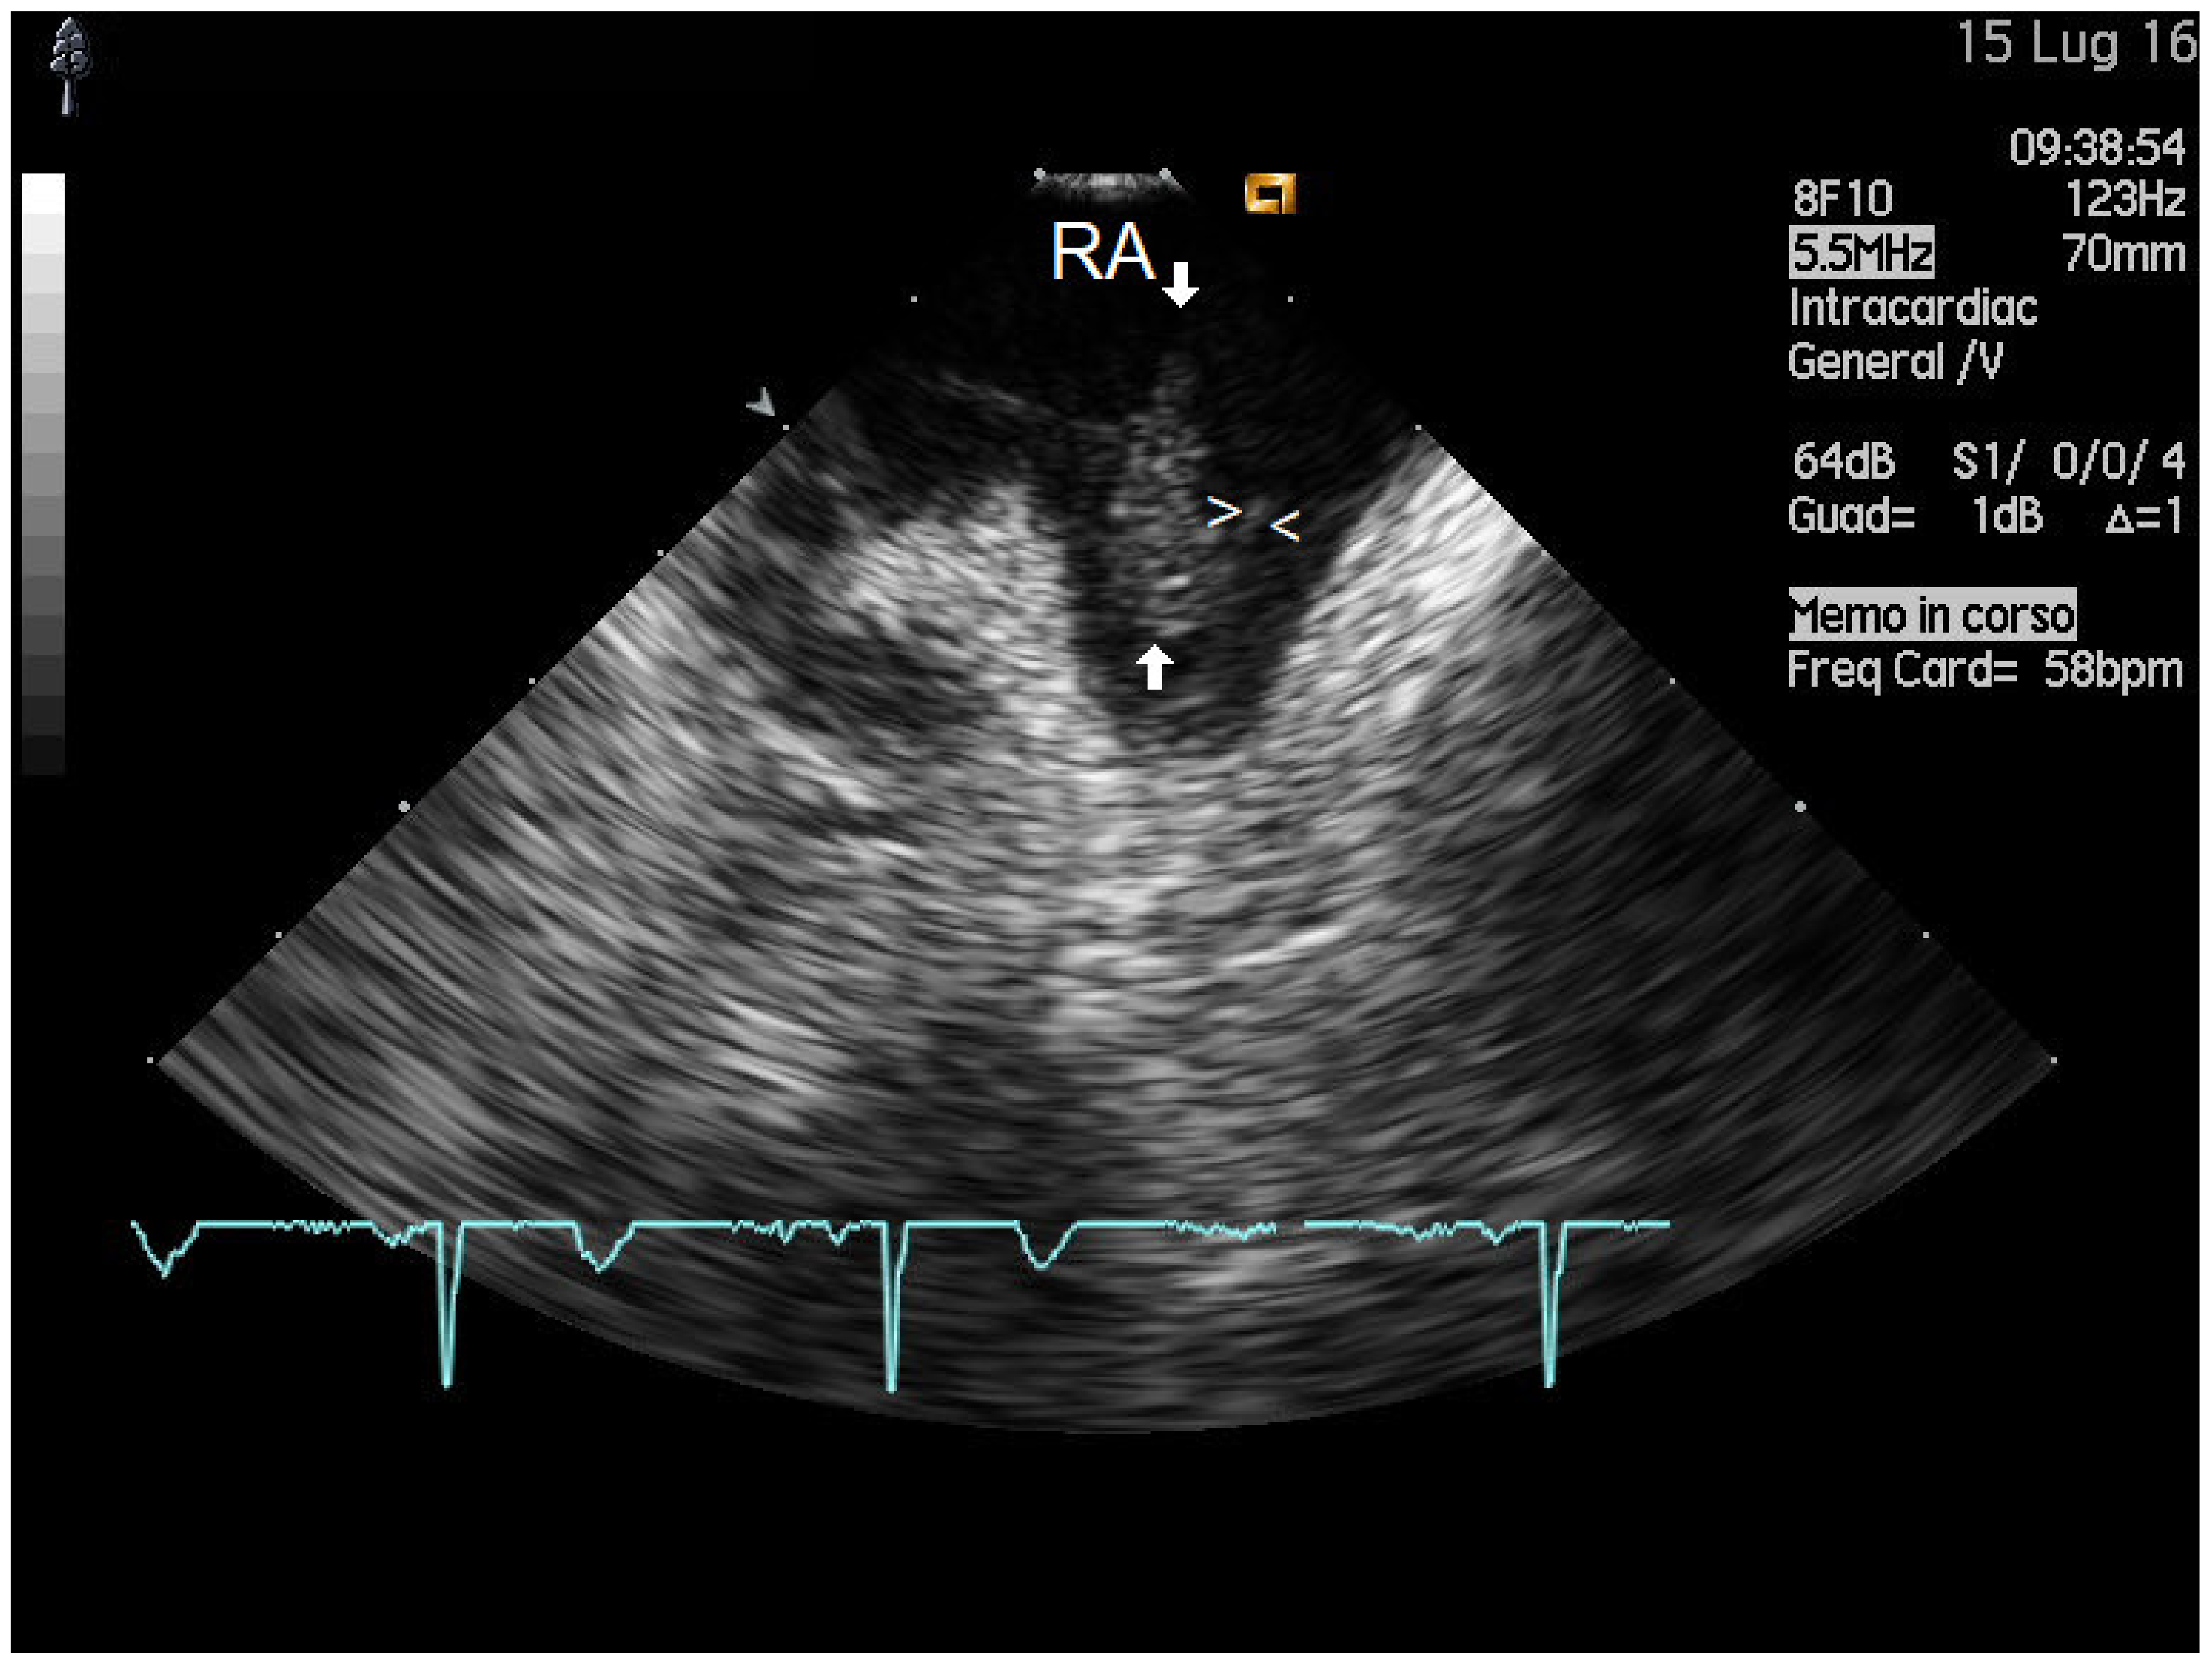

2.1. Mass Features and Associations

4.2. Intracardiac Echocardiography